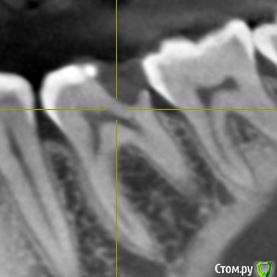

Сделала КЛКТ для того чтобы посмотреть насколько близко к пульпе располагается пломба. Однако материал данной реставрации оказался нерентгеноконтрастным. Так что только такой снимок зуба.

Также прилагаю снимок до лечения (там реставрация видна).

post-57670-0-00495500-1559651015_thumb.jpg